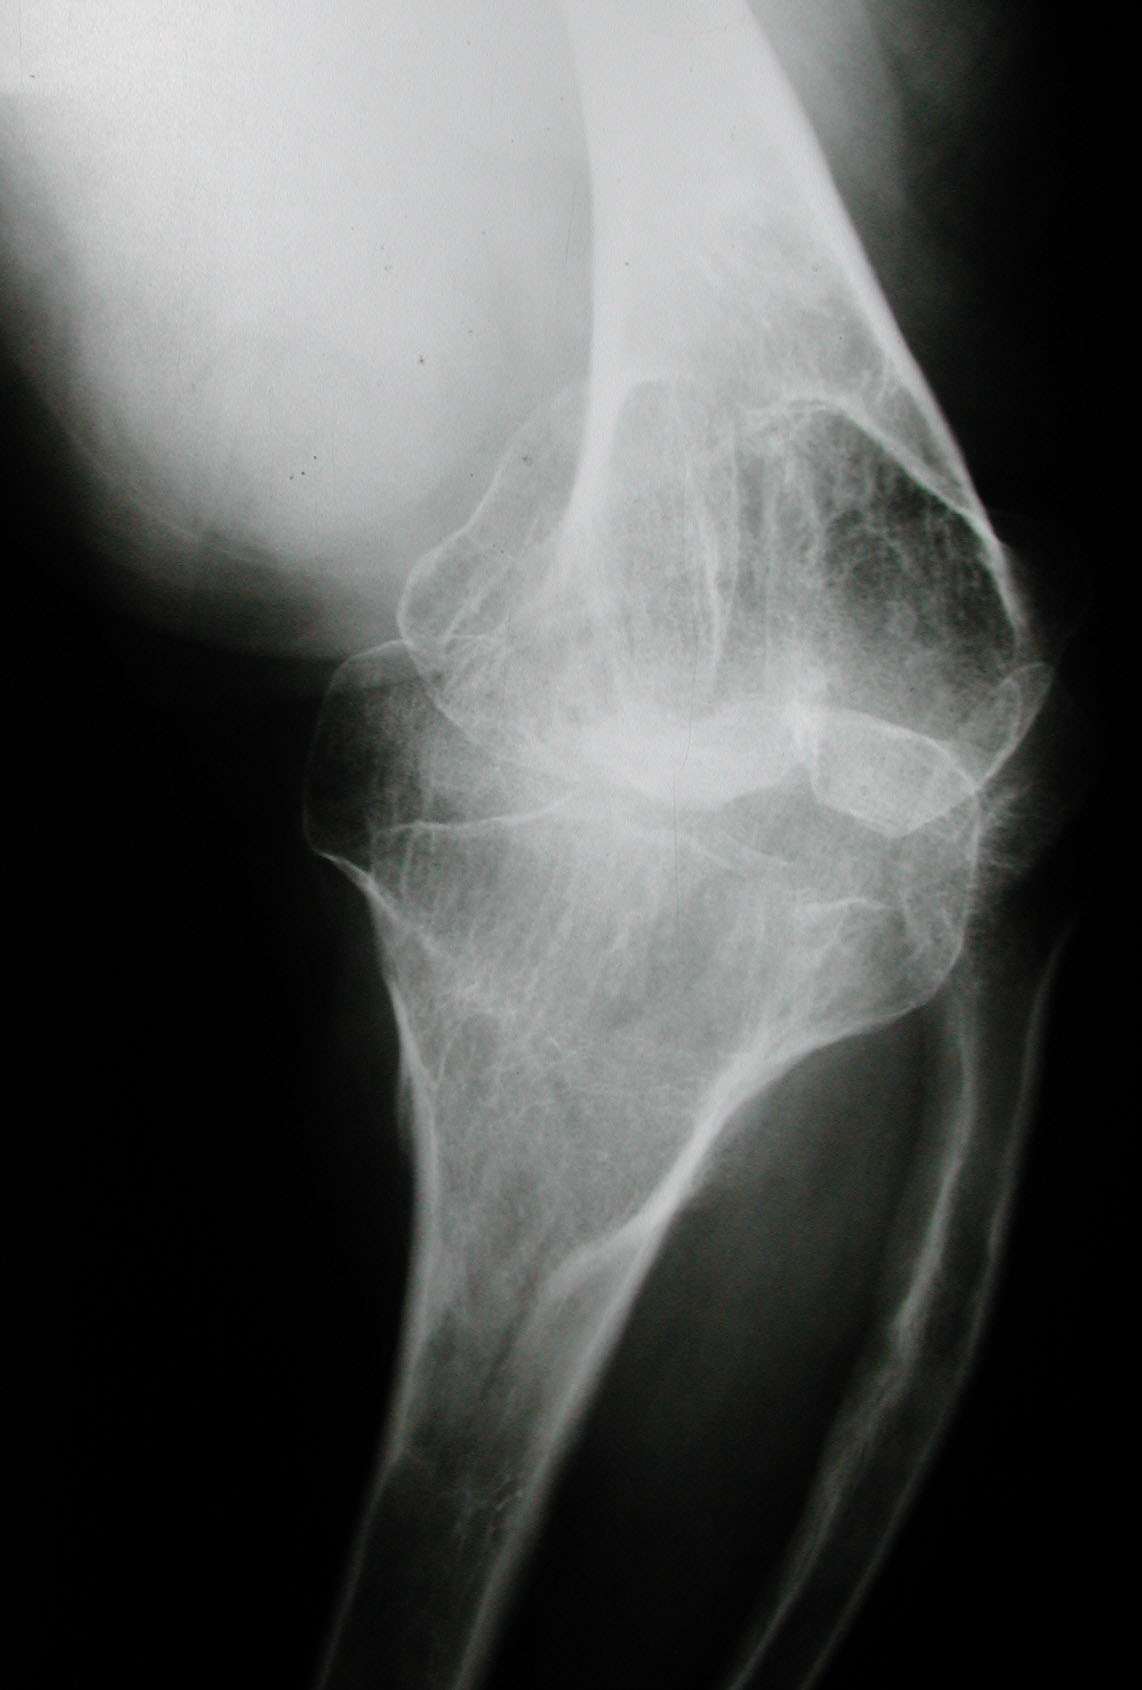

Seudoacondroplasia. [Pseudoachondroplasia]

7. Sekundiak TD. Total hip arthroplasty in patients with dwarfism. Orthopedics 2005;28(9):1075-8.

8. Huo MH, Salvati EA, Liberman JR, Burstein AH, Wilson PD Jr. Custom-designed femoral prostheses in total hip arthroplasty

done with cement for severe dysplasia of the hip. J Bone Joint Surg Am 1993;75:1497-1504.

9. Osagie L, Figgie M, Bostrom M. Custom total hip arthroplasty in skeletal dysplasia. International Orthopedic 2012;36:527-1.

10. Chiavetta JB, Parvizi J, Shaughnessy WJ, Cabanela ME. Total hip arthroplasty in patients with dwarfism. J Bone Joint Surg

Am 2004;86:298-303.

11. Ain MC, Andres BM, Somel DS, Fishkin Z, Frassica FJ. Total hip arthroplasty in skeletal dysplasias. Patients selection,

preoperative planning, and operative techniques. J Arthroplasty 2004;19(1):1-7.